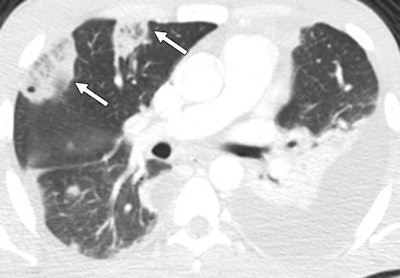

The group, led by Dr. Renata Almeida from Harvard Medical School, performed a retrospective analysis of chest CT scans acquired at their institution between 2007 and 2017 with a confirmed finding of septic PE due to abuse of IV substances, including opioids. For the 62 cases, nearly 60% had a reversed halo sign -- a focal rounded area of ground-glass opacity surrounded by a ring of consolidation.

Almeida and colleagues found that the reversed halo sign had a statistically significant association with septic PE in IV drug users (Cohen's kappa coefficient range, 0.84 to 0.96; p < 0.0001). They also found an average of two reversed halo signs per patient.

Reversed halo sign appears to be an "early and reliable imaging finding observed in most cases of CT-based diagnosis of septic PE secondary to IV substance use disorder" and should be included in the differential diagnosis of this patient cohort, the authors concluded.